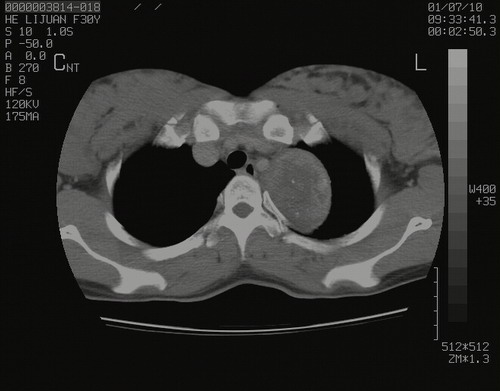

怀孕3个月时(2009-3至4月间),自述突感左侧前后胸疼痛1天,以前胸明显,随后偶感闷痛,余未见异

左肺尖脊柱旁沟肿块,境界清楚,边缘光滑,密度不均,内有多发点片状钙化,考虑良性肿瘤,骨软骨瘤或神经源性肿瘤可能,肺错构瘤不除外。

左后上纵隔见一类圆形肿块影,外侧边界清,密度不均匀,内可见点状钙化影,增强呈不均匀强化,考虑神经源性肿瘤可能。期待病理结果。